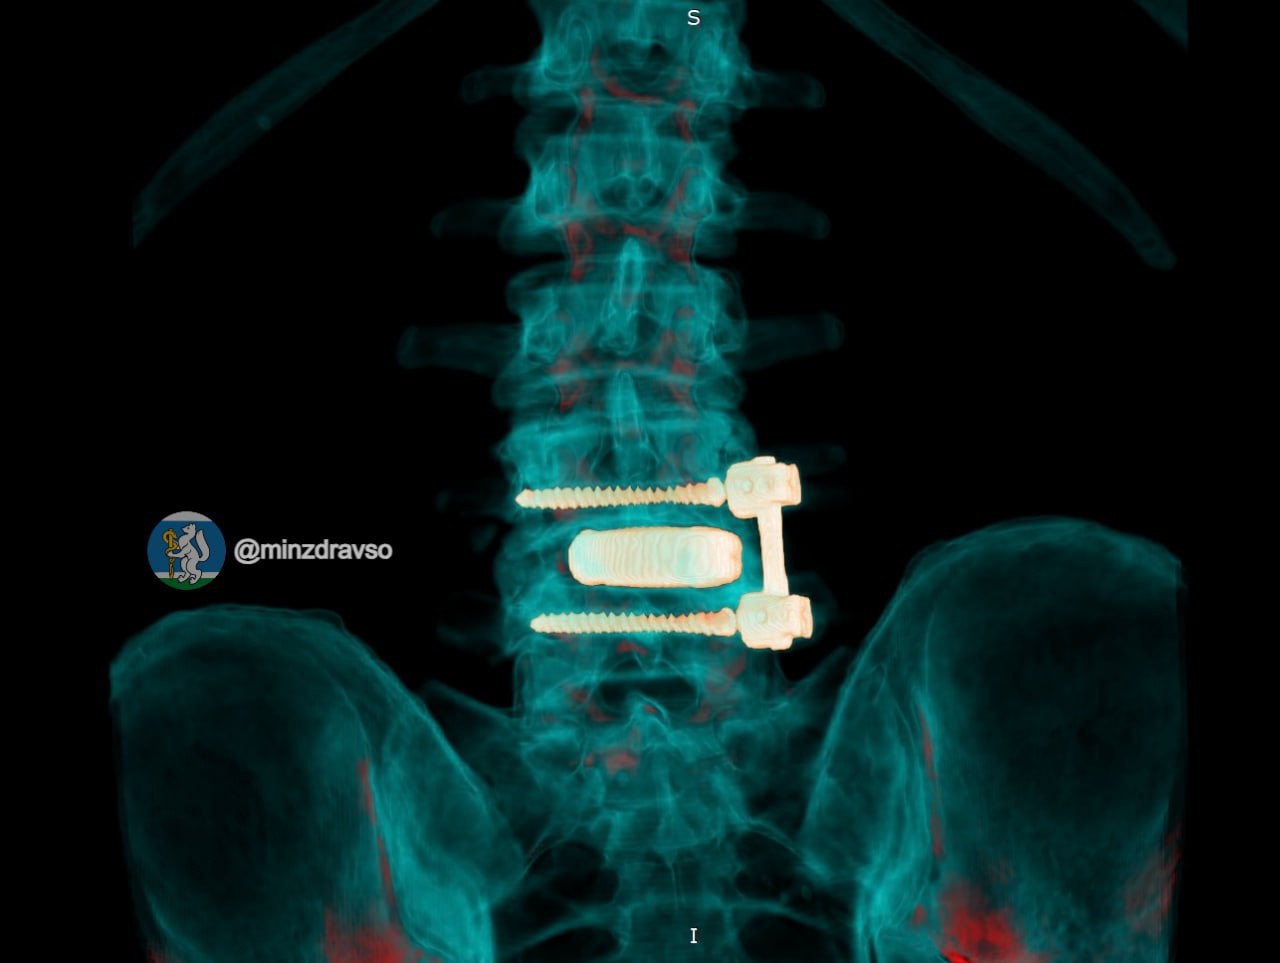

Фото: Минздрав Свердловской области

Нейрохирурги Свердловского госпиталя для ветеранов войн спасли 52-летнего водителя скорой помощи, у которого после давней операции на поясничном отделе позвоночника развилась инфекция.

Как рассказали в официальном телеграм-канале областного министерства здравоохранения «Здоровье уральцев», организм стал отторгать ранее установленную конструкцию, и у мужчины развилась периимплантная инфекция. Состояние резко ухудшалось: в какой-то момент водитель скорой упал из-за внезапной слабости и сломал лодыжку.

Лечить мужчину стали в госпитале для ветеранов войн, где ему сначала удалили инфицированную конструкцию и провели санацию очага воспаления, а затем после курса антибактериальной терапии восстановили опороспособность позвоночника с помощью титанового 3D-импланта, изготовленного по индивидуальным параметрам.

«Фиксацию выполнили российскими спонгиозными винтами. Уже в первые сутки после операции болевой синдром полностью купировался, пациент самостоятельно встал и начал ходить»,

– рассказали в Минздраве.